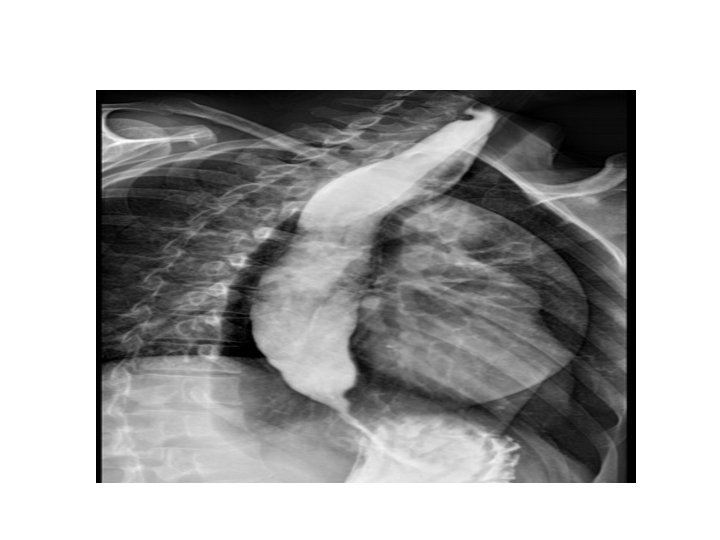

Barium Studies • Barium swallow: used to outline the pharynx and oesophagus. • Barium meal: used to outline the stomach and the first part of the small intestine • Barium follow through: used to outline the small intestine • Barium enema: used to outline the colon

Achalasia • Absent or reduced ganglions within the myenteric plexus • Mostly idiopathic • Can be caused by vitamin B 1 deficiency, Chagas disease and can be congenital • Dysphagia, weight loss, regurgitation • Heller’s procedure